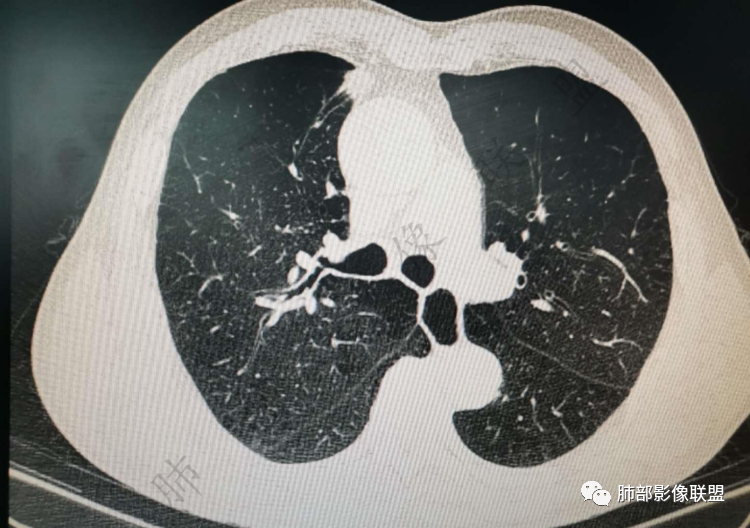

老年男性,炎性指标略高,肺气肿背景。右肺上叶胸膜下结节,部分边缘平直,部分稍模糊,软长毛刺,血管增粗,病灶中心密度减低,邻近脂肪间隙清晰。考虑炎性肉芽肿或慢性炎症,鉴别鳞癌。

淡泊人生 :

老年男性,炎性指标略高,肺气肿背景。右肺上叶胸膜下结节,部分边缘平直,部分稍膨隆,供血血管增粗,增强扫描病灶中心密度减低,呈环形强化,邻近脂肪间隙清晰。考虑炎性肉芽肿或慢性炎症,鉴别鳞癌。

右肺上叶前段胸膜下结节,边缘分叶毛刺,血管集束,支气管截断,纵膈胸膜牵拉,内乳动脉增粗,密度不均,中央可见坏死,两个月短期随访结节有增大,考虑恶性,腺癌。鉴别结核。

肺气肿背景,右肺上叶纵隔旁胸膜下结节,有血管集束,支气管堵塞,内乳动脉增粗,增强不均匀强化,内可见低密度区。考虑为恶性可能性大

老年男性,肺气肿背景,右肺上叶胸膜下弧立实性不规则结节,密度不均,其内低密度坏死影,支气管似有截断,血管集束,2月复查明显增大,考虑恶性,鳞癌可能大,鉴别炎性肉芽肿

老年男性,炎性指标略高。影像表现右肺上叶胸膜下结节,膨胀性生长部分边缘平直,边界清晰,病灶可见血管集束征,近段支气管阻断?增强扫描病灶中心密度减低,低密度区边界模糊,外围环形强化。老年性,不能排除恶性病变,周围性鳞癌,其次才考虑炎性肉芽肿或慢性炎症

老年男性患者。肺气肿 ,轻微的支气管扩张,右肺上叶前段胸膜下小结节影,轻分叶,长短不一毛刺,边界欠光整,明显的强化。考虑腺癌或鳞癌。

老年男性,肺气肿背景,右肺上叶前段胸膜下结节,部分边缘毛糙,血管集束增粗,支气管似有截断,胸膜牵拉,结节密度不均,两个月随访结节有增大,考虑恶性,肺癌可能;另右肺上叶后段肋胸膜区小片状类结节影,考虑炎性可能。

右肺上叶前段胸膜下结节,近段支气管截断,血管伸入结节内,密度不均,同侧临近内乳动脉增粗,不均匀强化,肺气肿背景,两月明显增大,考虑低分化鳞癌,隐球菌代排

老年男性,白细胞计数及CRP稍高,右肺上叶结节,两个月来有增大,部分边缘可见边界模糊的GGO,局部边缘平直、凹陷,临近胸膜增厚,内见坏死,坏死区边界未见明显壁结节,壁较厚而且均匀强化,支气管似乎有扩张然后截断,近端血管增粗明显。考虑炎性病变,脓肿?有结核病人密切接触史,注意是否为结核。有点难以理解的是为什么右侧内乳动脉增粗明显。

老年男性,无症状,炎性指标增高。肺气肿背景,右肺上叶前段结节,边缘部分平直部分澎隆,血管集束,支气管至病变边缘似截断,近端扩张。增强环形强化,中心坏死。两月内病灶增长太快,考虑炎性肉芽肿,慢性脓肿?结核?癌待排。